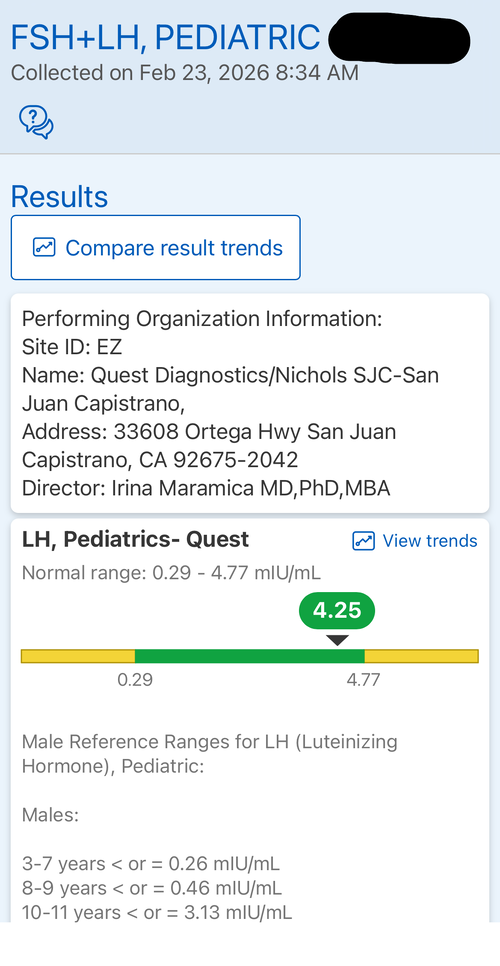

Introduction: The goal of this protocol is to hit my genetic potential. This is my first time experimenting with any pharmaceuticals. I am considering this based on my genetic potential allowing for more growth and the fact I need to take quick action if I want to hit my genetic target before my growth plates fuse. I may use an aromatase inhibitor but considering the fact my prior experience with pharmaceuticals is none I am fearful of having a “stack” of drugs and not having the resources to operate it well. I want to gain significant height in the most simple and low risk way possible. I will attach some blood work on my IGF-1, Cortisol, Testosterone and I have a bone age X-Ray which indicates my plates are open but estrogen exposure is starting the closure process. I will also attach a growth chart.

Introduction: The goal of this protocol is to hit my genetic potential. This is my first time experimenting with any pharmaceuticals. I am considering this based on my genetic potential allowing for more growth and the fact I need to take quick action if I want to hit my genetic target before my growth plates fuse. I may use an aromatase inhibitor but considering the fact my prior experience with pharmaceuticals is none I am fearful of having a “stack” of drugs and not having the resources to operate it well. I want to gain significant height in the most simple and low risk way possible. I will attach some blood work on my IGF-1, Cortisol, Testosterone and I have a bone age X-Ray which indicates my plates are open but estrogen exposure is starting the closure process. I will also attach a growth chart.